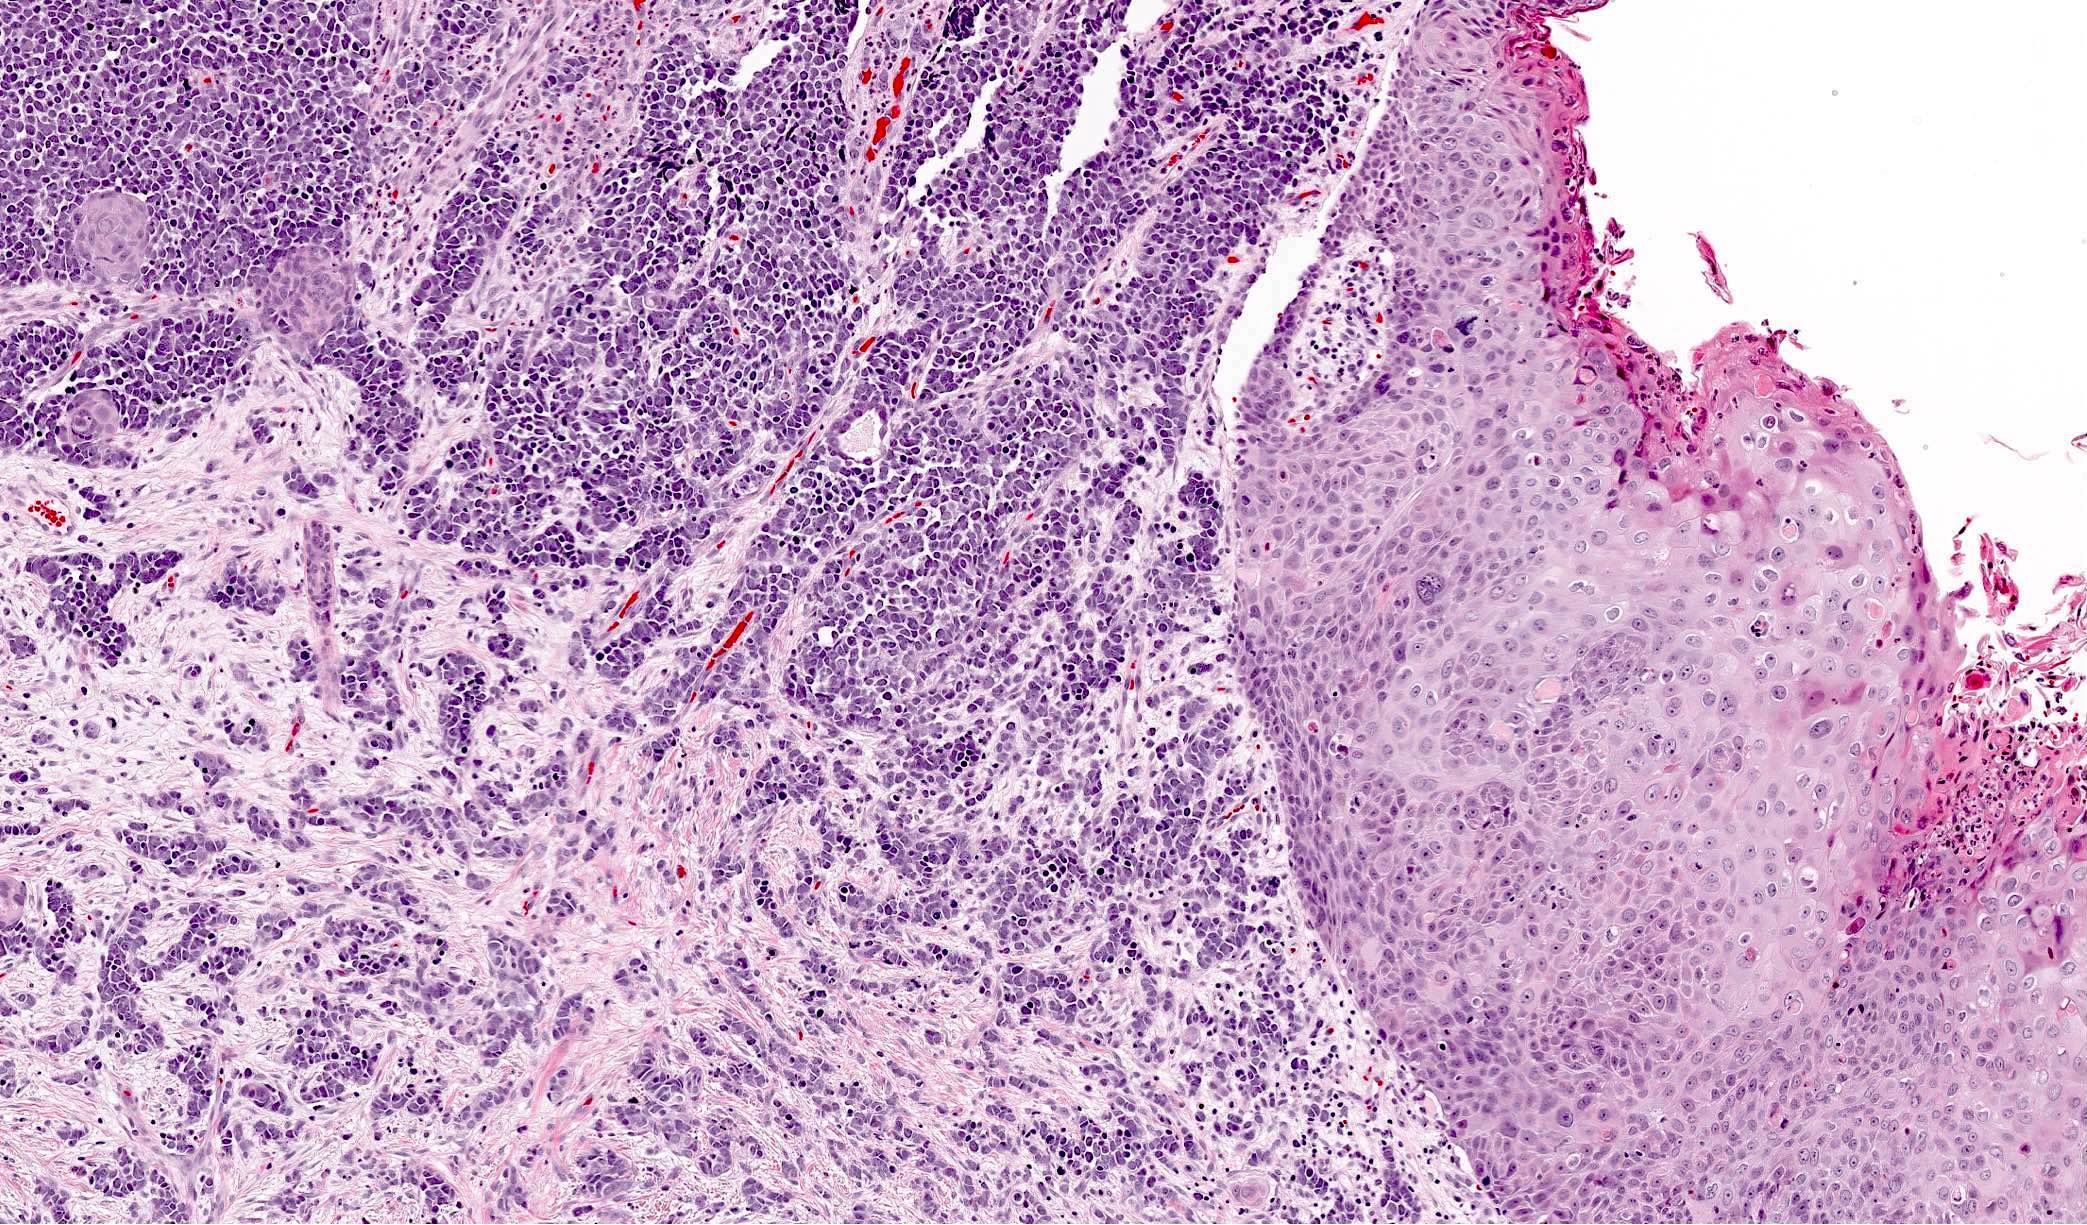

- Expansile, nodular or diffusely infiltrative tumor within the dermis, variably in subcutis

- Intraepidermal tumor (or component) is occasionally present

- Minority of cases feature neuroendocrine and other elements (combined Merkel cell carcinoma) such as divergent differentiation (e.g. squamous, sarcomatoid) or intimate association with other cutaneous neoplasms (most commonly in situ or invasive squamous cell carcinoma)